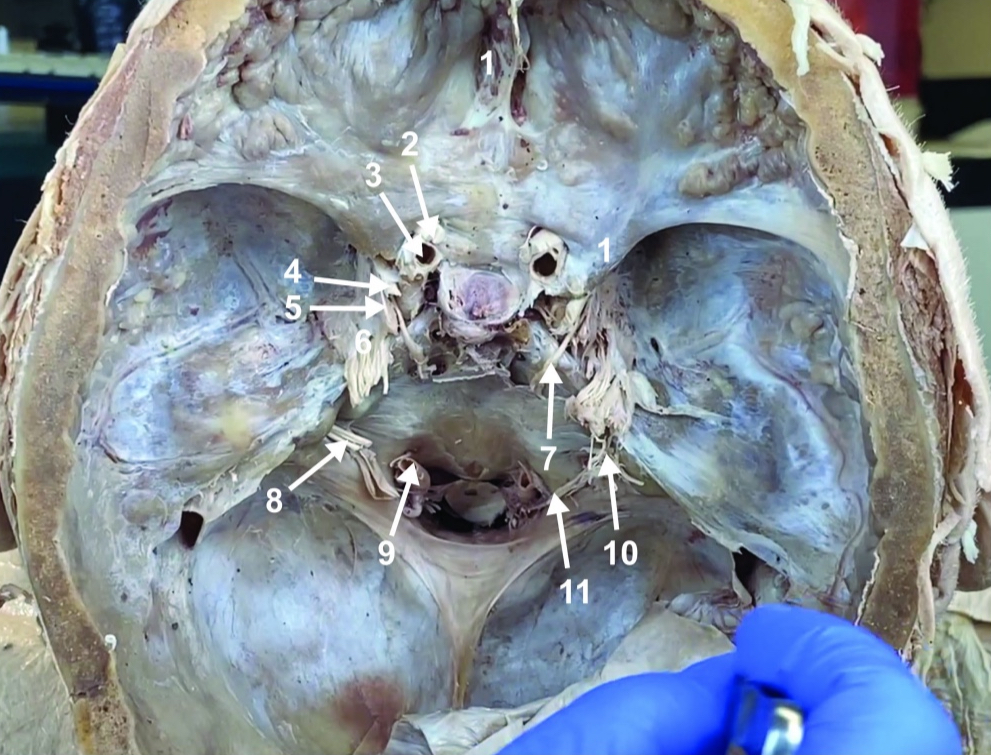

Foramen magnum

ID structure

Foramen ovale

ID structure

Foramen spinosum

ID structure

Cribiform plate

ID structure

Optic n. (CN II)

ID structure

Internal carotid a. (ICA)

ID structure

Occulomotor n. (CN III)

ID structure

Trochlear n. (CN IV)

ID structure

Trigeminal n. (CN V)

ID structure

Abducent n. (CN VI)

ID structure

Facial and vestibulocochlear n. (CN VII and VIII)

ID structure

Vertebral a.

ID structure

Glossopharyngeal and vagus n. (CN IX and X)

ID structure

Root of spinal accessory n. (root of CN XI)

ID structure

Ophthalmic division of CN V (CN V1)

ID structure

Maxillary division of CN V (CN V2)

ID structure

Mandibular division of CN V (CN V3)

ID structure

Foramen rotundum

ID structure

Foramen ovale

ID structure

Trochlear n. (CN IV)

ID structure

Abducent n. (CN VI)

ID structure